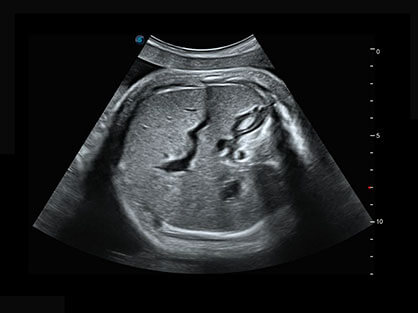

作为P系列家族成员之一,P40 Plus采用新葡的京集团8814检测站高端超声系统平台——极光,并以时尚秀丽、小巧灵动的外观设计绽放出灵动之韵、科技之美。高端平台的使用保证了P40 Plus优质的基础图像;完备的高级功能可满足您全身应用的基本需求;丰富的探头配置、多样的高级4D成像及分析软件为您日益增多的妇产应用需求提供丰富的诊疗方案。

结合新葡的京集团8814检测站超宽频带探头技术优势,能够更好地获得高分辨力与高穿透力的平衡,保证图像质量,为临床诊断保驾护航。

微米成像技术提升了对组织斑点噪声信号的抑制能力,并进一步强化边界信息,从而获得清晰图像。